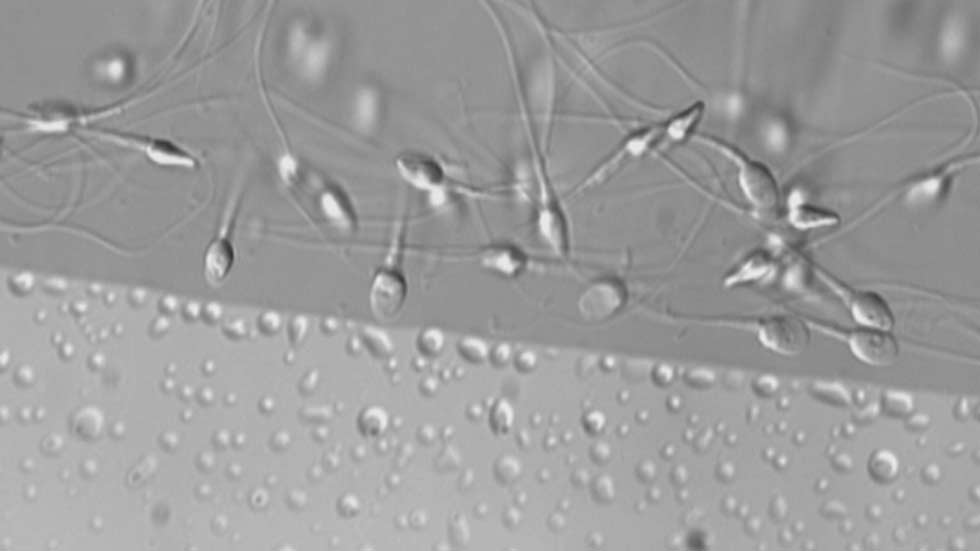

Aproximadamente tres de cada diez hombres en edad fértil tiene semen de mala calidad, inferior a los estándares marcados por la OMS. Son datos que se han presentado en un congreso sobre reproducción asistida que se celebra en Madrid. Factores ambientales, el estrés o una mala alimentación están detrás en la mayoría de los casos.